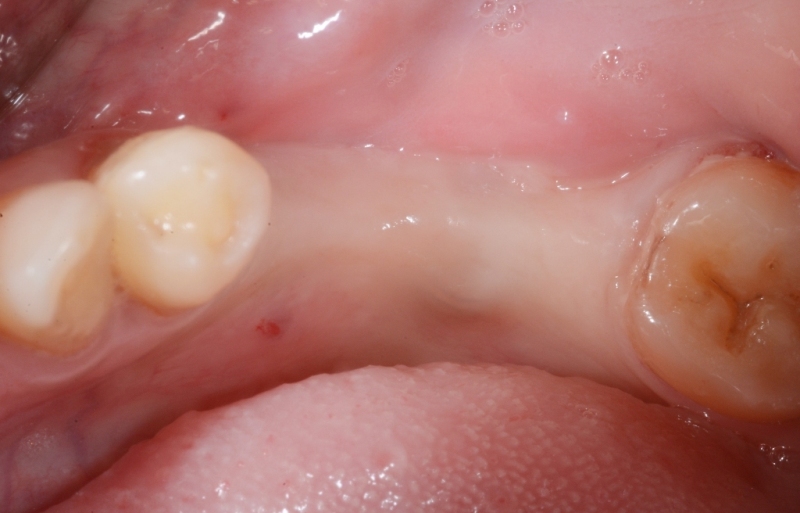

牙肉重建術案例

案例1

牙肉重建術前

牙肉重建術後